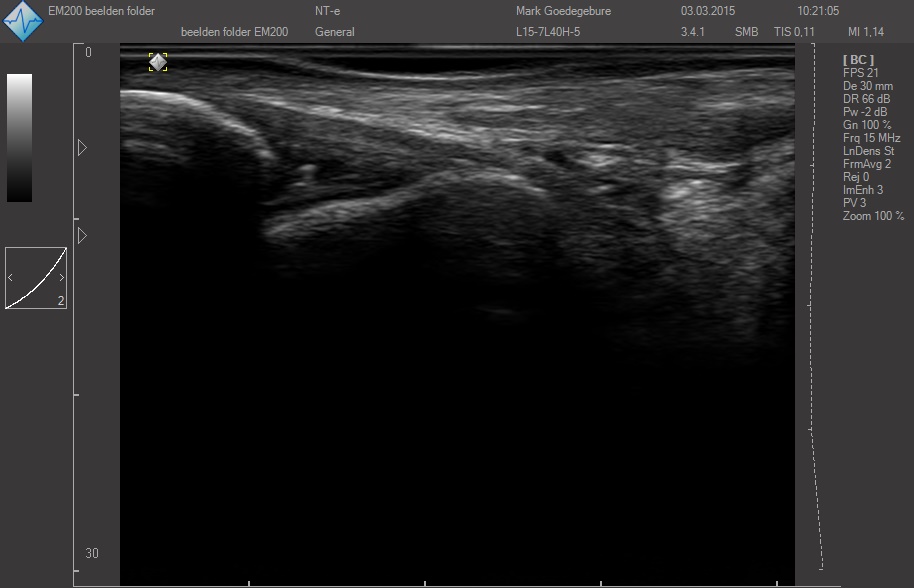

ЗДЕСЬ Вы можете посмотреть реальные кинопетли с аппарата УЗИ SmartUs.